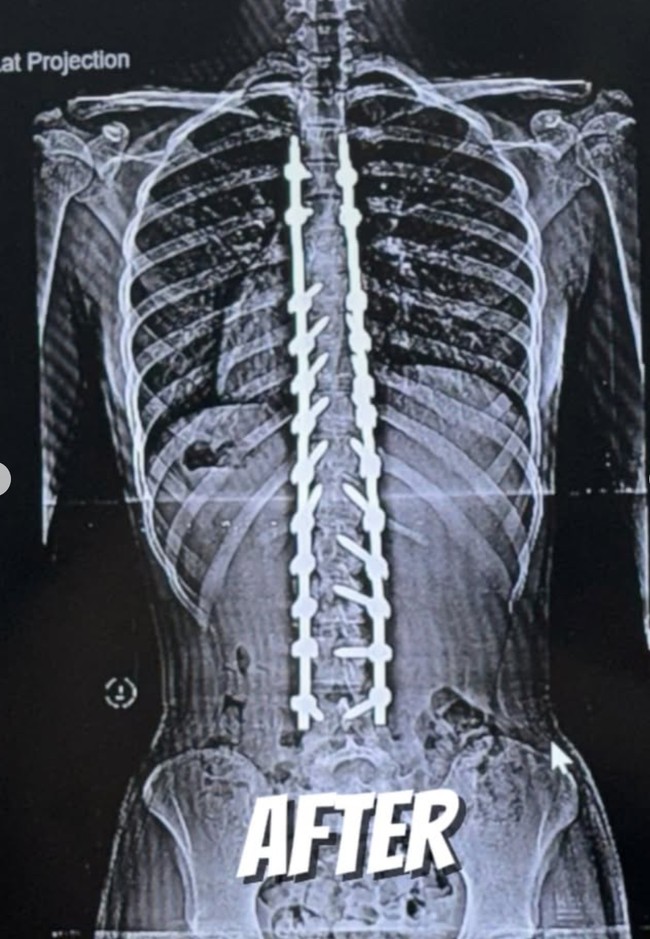

Jakarta - Putri angkat Deddy Corbuzier, Nada Tarina Putri beberapa waktu lalu menjalani operasi skoliosis. Melalui akun Instagram, Nada membagikan perjalanan operasinya.